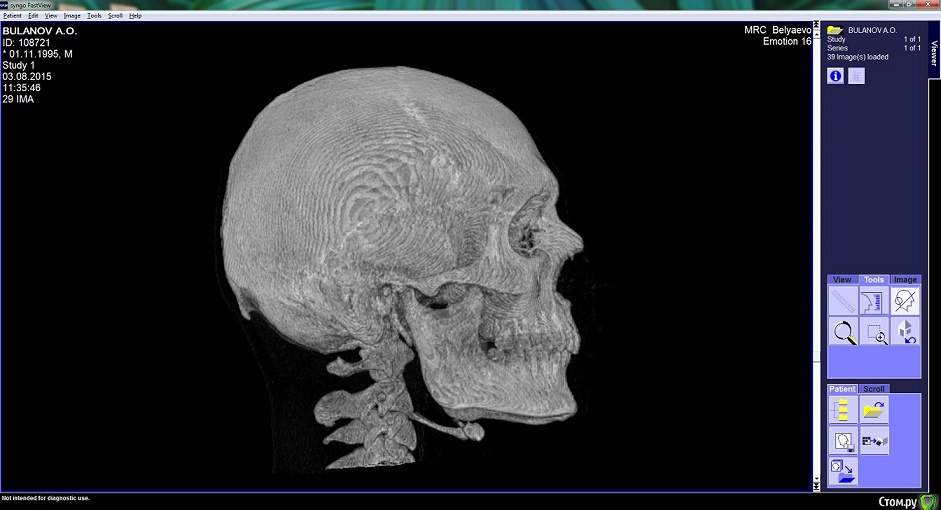

Arseny0111 Опубликовано 27 сентября, 2015 Поделиться Опубликовано 27 сентября, 2015 (изменено) Здравствуйте,в ходе драки получил удар,в верхнюю челюсть,сразу же не значительно сменился прикус и искривилась носовая перегородка.Есть ли на снимках отклонения от нормы?трещина?и т.д.Что с этим делать к кому обращаться?Из исследований дополнительно имеется МСКТ(3D)Спасибо. Изменено 27 сентября, 2015 пользователем Arseny0111 Ссылка на комментарий

Arseny0111 Опубликовано 1 октября, 2015 Автор Поделиться Опубликовано 1 октября, 2015 Здравствуйте,в ходе драки получил удар,в верхнюю челюсть,сразу же не значительно сменился прикус и искривилась носовая перегородка.Есть ли на снимках отклонения от нормы?трещина?и т.д.Что с этим делать к кому обращаться?Из исследований дополнительно имеется МСКТ(3D)Спасибо.Уважаемые доктора,помогите пожалуйста.Неужели нет компетентных специалистов в этой области? Ссылка на комментарий